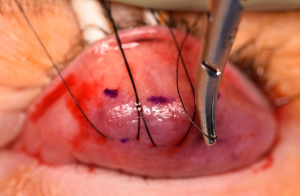

Step 4[1][8][11]

Now elevating the conjunctiva and Müller’s muscle with the suture, a Putterman Müller’s muscle–conjunctival resection clamp is placed at the border of the superior tarsus and clamped shut, sandwiching the conjunctiva and Müller’s muscle (Figure 6A).

This clamp has three needles which penetrate through the squeezed conjunctiva and Müller’s muscle so that they do not slip out of the clamp, ensuring the correct desired amount of tissue will be resected (Figure 6B).

Occasionally, tarsus may inadvertently be incorporated into the clamp, which is not desired (Figure 6C). If the tarsus has been incorporated, the margin of the lid may be distorted. To evaluate for this, the Desmarres retractor or q-tip is removed, the lid is inverted back into normal position, and the contour of the margin is assessed. If the contour is not normal, tarsus may have been inadvertently grasped by the clamp and the clamp readjusted to allow the tarsus to be pulled gently free.

Figure 6A) A Putterman clamp is then placed so that the tented apex of the tented Muller’s/conjunctiva complex is between the clamp. B,C) Care must be taken to ensure the teeth are placed at the superior margin of the tarsus only, and that tarsus has not been inadvertently incorporated into the clamp. Photo courtesy of Adham al Hariri, M.D.